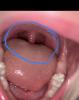

Мамы, это и есть "красное горло"?